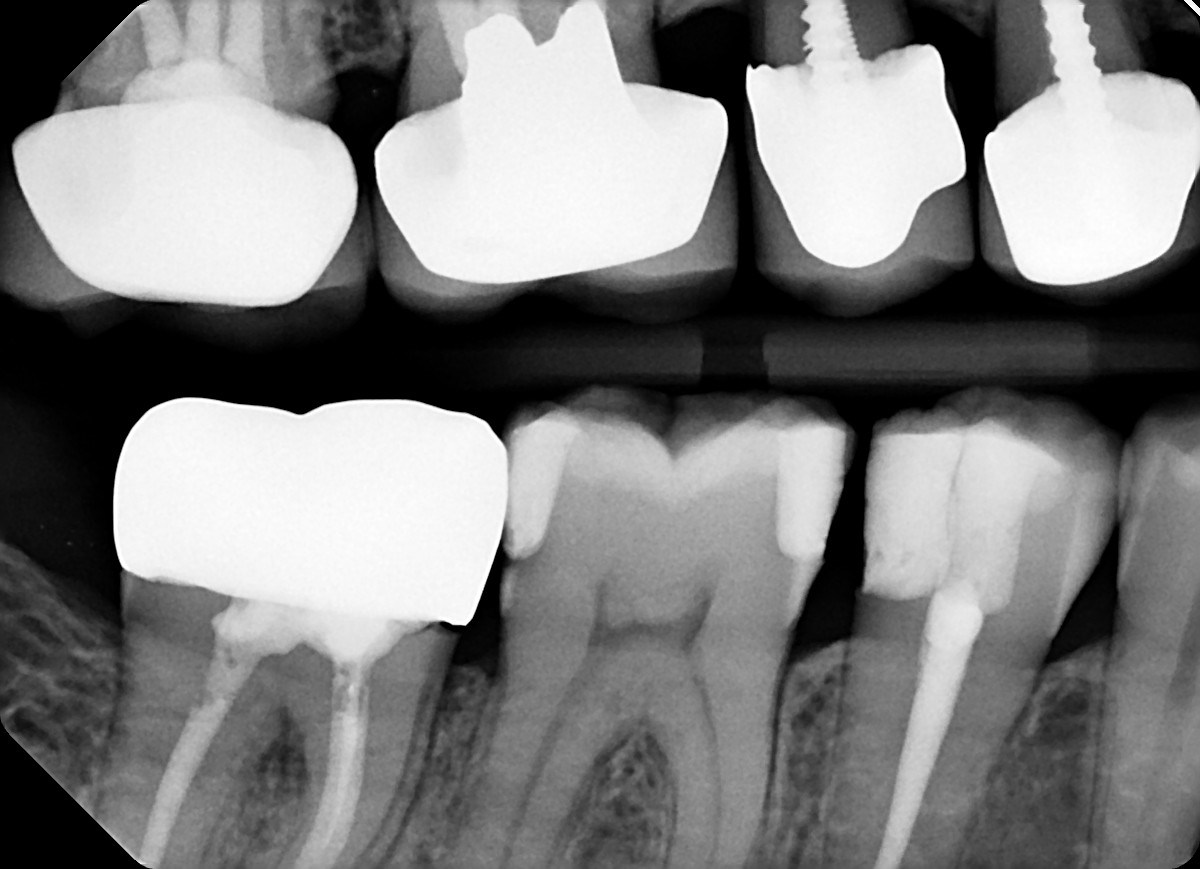

6. On which surface a recurrent caries can be detected?

7 / 35

7. On which surface a recurrent caries can be detected?

No cavity can be detected, restorations on 1.7, 4.6 and 4.7 are porcelain onlays